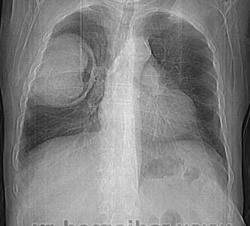

Правое легкое: в проекции средней доли (S3,4,5) определяется объемное образование преимущественно однородной структуры с ровными, четкми контурами размерами 92х88х94мм. Плотность его составляет 19-25 едН. В медиальных отделах образования содержится серповидная полоска воздуха. Латеральные отделы образования выходят за контуры грудной полости на 42 мм. На этом участке ребра не дифференцируются. Внутренний контур передней зубчатой, подлопаточной мышц размытый, граница между образованием и ними отчетливо не видна. Кзади от образования, в кортикальных отделах в легочной ткани инфильтрация. Кпереди от описанного образования расположен участок, широким основанием прилежащий к грудной стенке, имеющий плотность 12-20 ед.Н, однородную структуру, размеры 14х48мм. Прилежащее ребро интактно.

Наблюдение на самом деле весьма редкое и интересное. Для начала; это не эхинококк и конечно не мезотелиома. Данные заболевания не дают такую скиалогическую КТ картину: полость с содержимым, серпом воздухом и с деструкцией рёбер, лопатки и инвазией грудной стенки. Такой агрессивный характер инфекции может быт при актиномикозе; но при нём идёт диффузный процесс; не характерно образование таких больших полостей с внутренними включениями.

Аспергиллус может расти инвазивно и вызывать деструкцию в костях; есть отдельная форма: инвазивный аспергиллёз... Я прикрепил ниже сканы аспергиллёза с инвазией основания черепа. Но для неё не характерно образование полостей с "грибковым шаром"... Это признак мицетемы (отдельная форма аспергиллёза). Если поразмыслить логически; должен быть субстрат; а потом уже "сел" гриб. Я думаю дело было так; у пациента есть в наличии мелкоклеточный рак лёгкого или туберкулёзная полость; а потом присоединился аспергиллус и мы получили представленную картину. По другому никак не укладывается. ИМХО.

Наблюдение на самом деле весьма редкое и интересное. Для начала; это не эхинококк и конечно не мезотелиома. Данные заболевания не дают такую скиалогическую КТ картину: полость с содержимым, серпом воздухом и с деструкцией рёбер, лопатки и инвазией грудной стенки. Такой агрессивный характер инфекции может быт при актиномикозе; но при нём идёт диффузный процесс; не характерно образование таких больших полостей с внутренними включениями. Аспергиллус может расти инвазивно и вызывать деструкцию в костях; есть отдельная форма: инвазивный аспергиллёз... Я прикрепил ниже сканы аспергиллёза с инвазией основания черепа. Но для неё не характерно образование полостей с "грибковым шаром"... Это признак мицетемы (отдельная форма аспергиллёза). Если поразмыслить логически; должен быть субстрат; а потом уже "сел" гриб. Я думаю дело было так; у пациента есть в наличии мелкоклеточный рак лёгкого или туберкулёзная полость; а потом присоединился аспергиллус и мы получили представленную картину. По другому никак не укладывается. ИМХО.